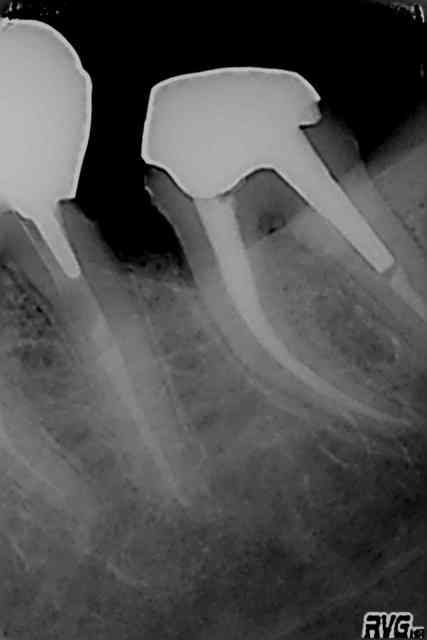

Je me suis mis à faire des IC+CCM en une emprteinte il y a un an. Je tiens des stats sur mes prothèses.

Heureux hasard il y a un mois je m'étais fait un petit bilan pour voir factuellement si c'était une bonne au mauvaise chose.

Bilan : le tableau est sans appel (NB la plus haute colonne est de l'ordre de 20% environ, j'ai viré les chiffres :p).

En une étape c'est un peu moins bien, les sources d'erreurs étant plus nombreuses, mais rien non plus de dramatique : le nombre d'échec (couronne a refaire d'emblée) est quasi identique par exemple.

Je ne fais des empreintes IC+CCM que lorsque je n'ai plus de rebords sur la dent ( a raz la gencive quoi) ou alors avec un seul rebord. Deux rebords ou trois rebords court c'est IC et trois rebords et plus c'est RCR.

Le principale défaut de cette technique, c'est que les préparations doivent être plus ou moins à raz la gencive. De plus, personnellement, j'ai du mal à évaluer la futur épaisseur de céramique sans voir le faux moignon (IC ou compo).